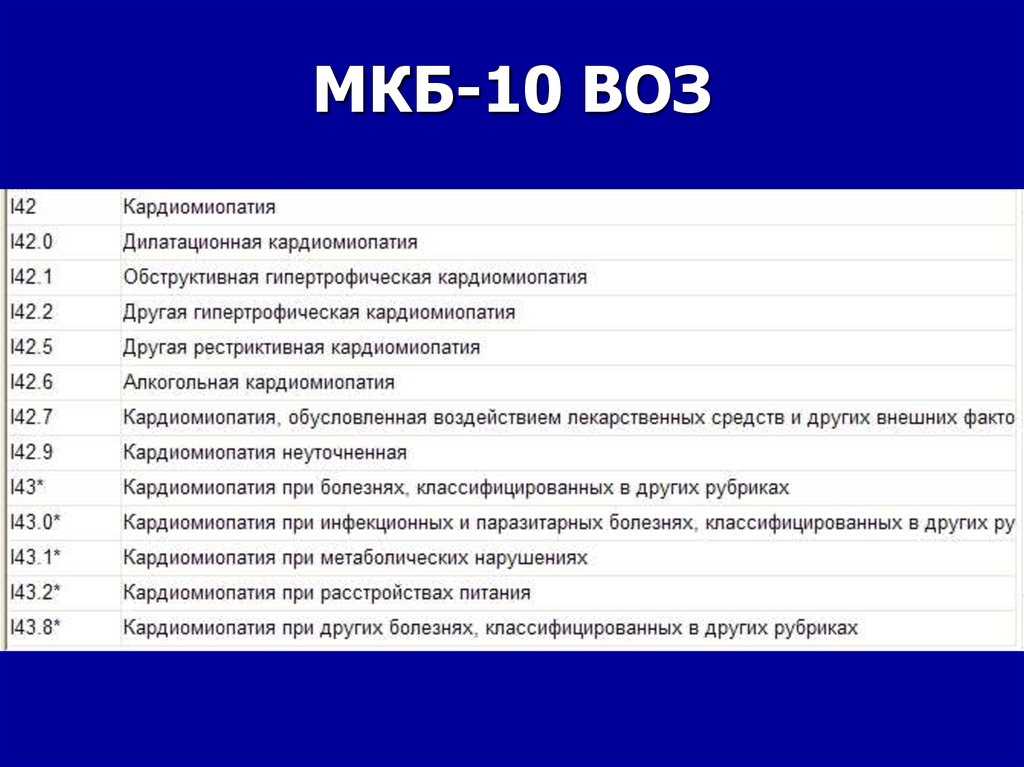

Код мкб 10 атерома головы

Код мкб 10 атерома головы 109 фото